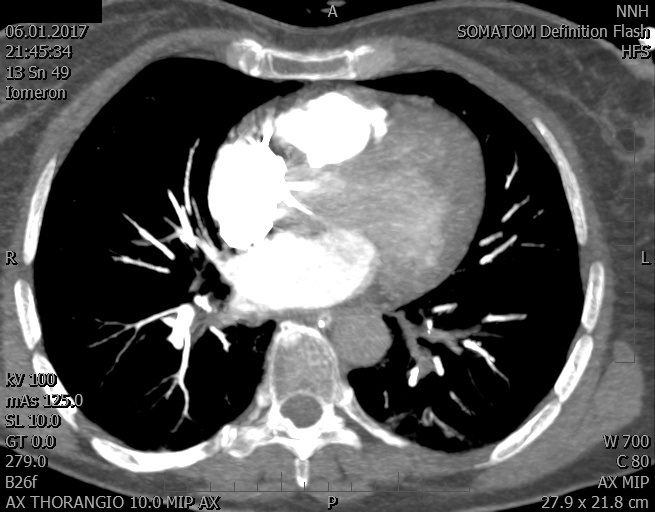

Video 2 - Echokardiograficky byla zjištěna těžká dysfunkce dilatační levé komory s nezvětšenou pravou komorou.Pro nejasnou příčinu zástavy jsme provedli i vyšetření výpočetní tomografií (CT), které vyloučilo plicní embolizaci (série 1 - soubory na konci článku). V den přijetí při přetrvávající oběhové nestabilitě byla nemocná opakovaně defibrilována pro fibrilaci komor se stabilizací rytmu po podání amiodaronu a mesocainu. Dle hemodynamických měření se jednalo o těžký kombinovaný šok. Vstupní laboratorní vyšetření bylo bez větších pozoruhodností. Posléze jsme doplnili anamnézu od příbuzných a zjistili, že pacientka užila do dvou hodin před srdeční zástavou první tabletu amoxicilinu na lehký respirační infekt. Při nevýtěžnosti vstupních vyšetření a nových anamnestických informacích jsme doplnili 14 hodin po kolapsu vyšetření koncentrace tryptázy v séru, která byla extrémně zvýšena (tabulka 2), což nás vedlo k podezření na anafylaxi.